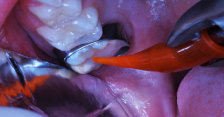

An RMGI bioactive ionic resin-based composite was injected after a self-etching bonding agent was applied.

Figure 8

Light exposure was applied for 20 seconds.

Figure 9

The occlusal-distolingual tooth preparation was completed, and a stainless steel orthodontic band was pressed into place to serve as a matrix (Figure 7). After two 60-second applications of a 5% glutaraldehyde/HEMA desensitizing solution, a self-etching bonding agent was painted on the enamel surfaces. An RMGI bioactive ionic resin-based composite was then injected in two portions (Figure 8), with 10-second light beam exposure between the injections. After the material was injected to overfill, the light beam was applied once more, for 20 seconds (Figure 9). The restoration was then trimmed and finished in the usual manner using large, round diamond burs at slow speed and diamond finishing burs on the axial surfaces (Figure 10). The self-etching bonding agent was then applied as a final glaze, and occlusal contacts were adjusted using articulating paper as a guide.